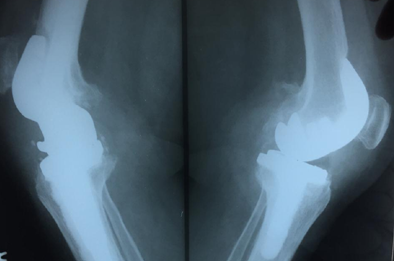

Knee Replacement